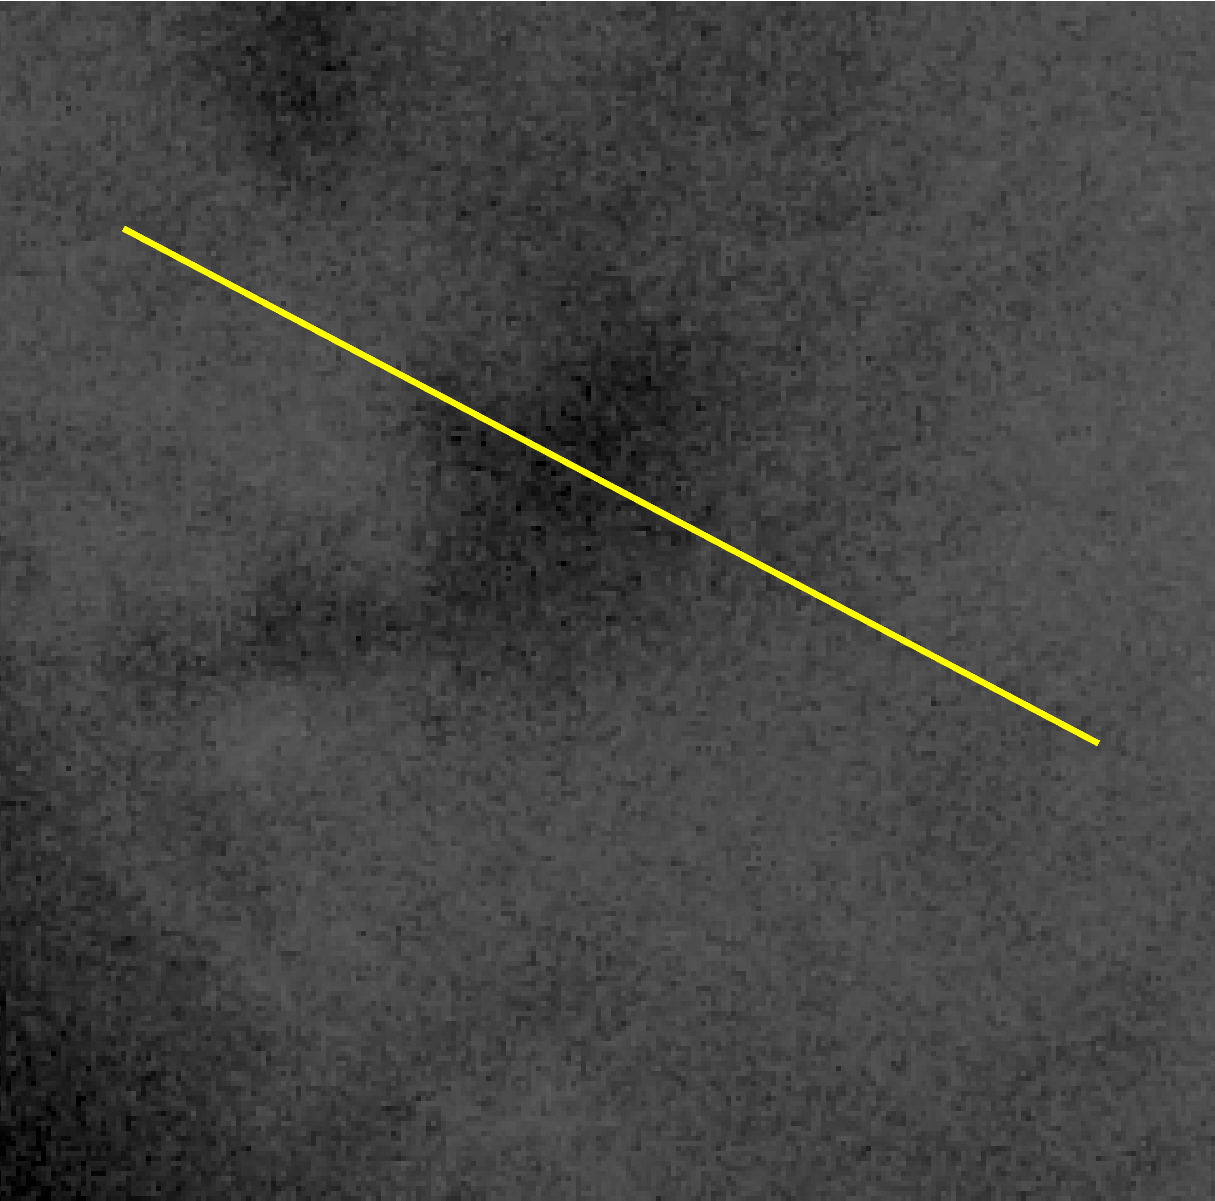

Marangoni effect-dominated thinning is characterized by strong, outward flow and small evaporation rates. Figure 4 shows the fit to the S10v1t6 12:30 spot as an example; the data for the fit is shown in Figure 3.

The S10v1t6 12:30 spot is a distinctive breakup instance because it is partially hidden by eyelashes and develops very quickly in the later half of the trial, as seen in Figure 3b. We fit this instance with two ghost time levels for several reasons. Once the eyelash and lid move so the location where FT-TBU forms is visible, there is already substantial decrease in the measured FL intensity in the center of breakup–a 50% difference as compared to the edges of the breakup region. If we compare this to the S18v2t4 7:30 spot, which we choose to fit with a single ghost time level, the latter shows only a 20% difference between the measured FL intensity at the center of breakup and at the edges of the breakup region (see Figure 2 of Online Resource 1). Secondly, fitting the S10v1t6 12:30 spot instance with a single ghost time level results in a 21% increase in the residual, indicating a significantly worse fit.

Refer to caption

(a)

(b)

(c)

Figure 3: Extracted data for the S10v1t6 12:30 spot. In (c) the image has been brightened and contrast-enhanced.